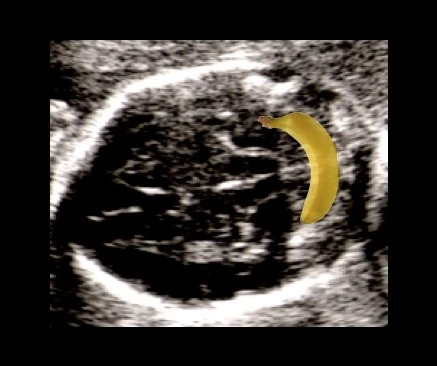

Sinal da banana: o cerebelo, normalmente redondo, assume uma curvatura em forma de banana porque seus hemisférios são puxados para baixo. A cisterna magna deixa de ser visualizada. É o sinal de maior sensibilidade para mielomeningocele — aparece em 72 a 100% dos casos antes de 24 semanas. Após 24 semanas, o cerebelo pode desaparecer completamente do campo de visão (deslocamento total para o canal cervical), o que também é um sinal importante.

Sinal da banana no ultrassom — cerebelo com formato curvo característico da mielomeningocele